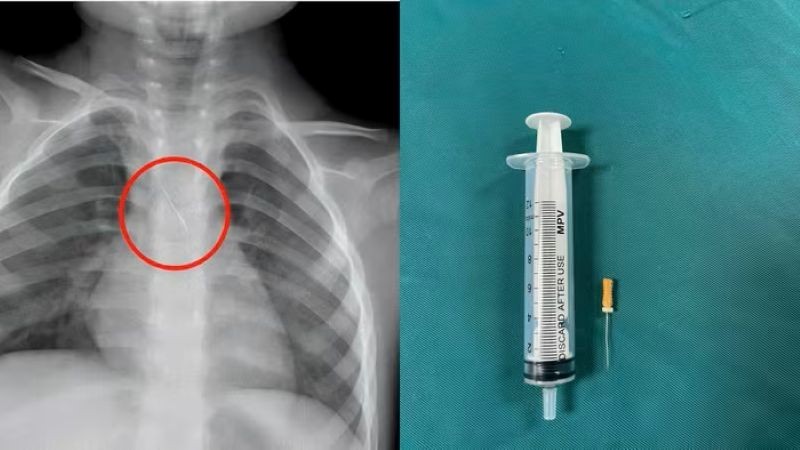

Ngày 15/11, Bệnh viện Đa khoa tỉnh Quảng Trị cho biết vừa cấp cứu thành công một cháu bé 3 tuổi bị kim chọc tủy dài 22mm rơi vào đường thở.

Dị vật trong đường thở của bệnh nhi. (Ảnh: Bệnh viện Đa khoa tỉnh Quảng Trị)

Trước đó, bệnh viện tiếp nhận bệnh nhi N.Q.T.Đ, 3 tuổi, trú tại xã Cửa Việt, Quảng Trị trong tình trạng ho nhiều, ho sặc. Kết quả chụp phim cho thấy 1 dị vật kim loại dài khoảng 22mm nằm ở góc carina (vị trí chia đôi khí quản) đe dọa gây tắc nghẽn đường thở.

Ngay lập tức, các bác sĩ hội chẩn liên khoa và quyết định nội soi phế quản cấp cứu. Dị vật được phát hiện có một đầu nhọn cắm vào 1/3 dưới khí quản, đầu còn lại nằm trong phế quản gốc trái.

Sau 15 phút thao tác khẩn trương, dị vật được kíp mổ lấy ra an toàn. Bé trai cải thiện triệu chứng ngay sau can thiệp và xuất viện sau 48 giờ theo dõi.

Theo gia đình bệnh nhi, khi đang được làm răng, kim chọc tủy bất ngờ rơi từ khoang miệng xuống đường thở của bé. Đây là trường hợp hy hữu có thể gây hậu quả rất nặng như xẹp phổi, viêm phổi, áp xe phổi, tràn khí màng phổi, thậm chí tử vong nếu không được xử trí kịp thời.